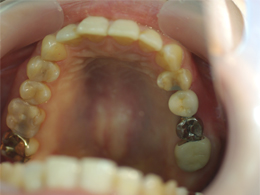

左上の奥歯の骨が少なくてそのままではインプラントを入れられなかったため、オペと同時にサイナスリフトをしました。

今ではしっかり噛めています。骨が極度までない場合でもほとんどがインプラントオペと同時にサイナスリフトが可能です。